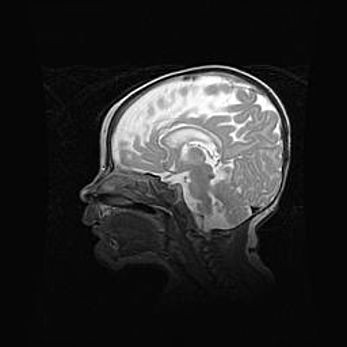

Аномалия Денди-Уокера. Признаки гипоплазии мозолистого тела.

Возраст: 5 месяцев 3 дня

Вес: 5550 г

Пол: мужской

Окружность головы: 39 см

Срок гестации: 40 недель

Аномалия Денди-Уокера – это порок развития головного мозга, для которого характерна триада симптомов: гипотрофия или аплазия червя мозжечка и/или полушарий мозжечка, расширение четвёртого желудочка с формированием ликворной кисты задней черепной ямки, гипертензионная гидроцефалия различной степени.

Гипоплазия мозолистого тела относится к дефектам внутриутробного этапа развития мозговой ткани, возникающим в процессе закладки структур головного мозга, что происходит на начальных этапах развития эмбриона.